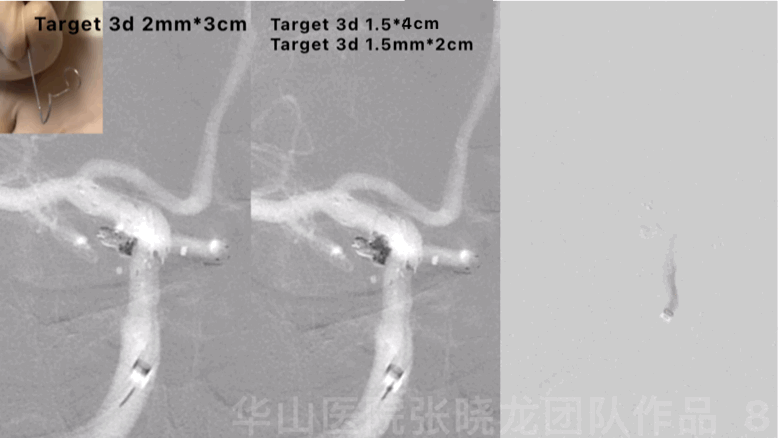

Figure 8 GIF. Lateral spiral curved Echelon-10 was re-navigated into the sac and inserted 3 coils (Target 3d 2mm*3cm, 1.5mm*4cm, 1.5mm*2cm). Angiograms showed the aneurysm was densely packed and parent artery was patent.

图 8 GIF. Echelon-10重新塑螺旋形后超选入动脉瘤腔内,依次填入3枚弹簧圈(Target 3d 2mm*3cm, 1.5mm*4cm, 1.5mm*2cm)。复查造影动脉瘤致密栓塞,载瘤动脉通畅。